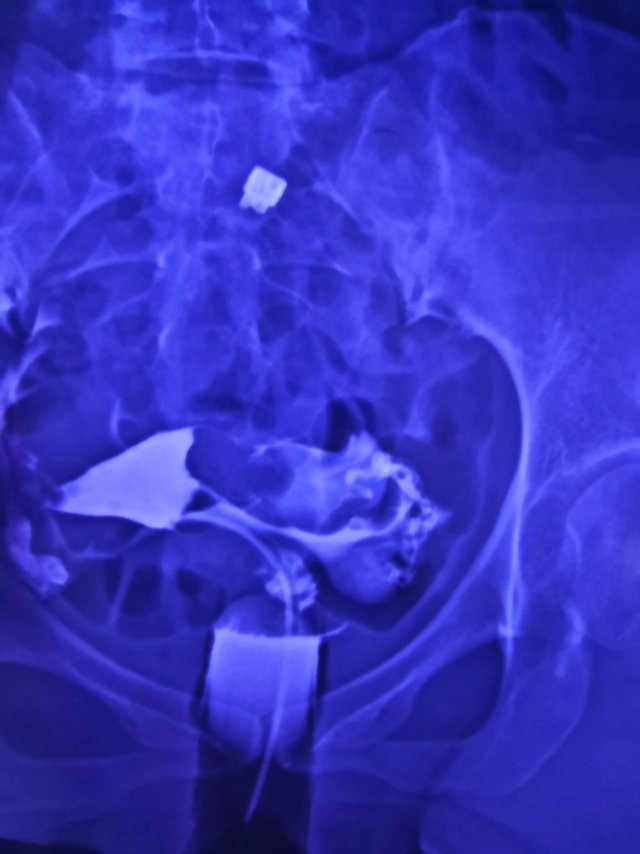

输卵管造影两年前的需要手术吗

这种必须做手术么还是取了胚胎不是非要做

这个手术不是非得要马上做,需要根据你的年龄、生育计划等来综合评估并权衡利弊后再决定是否需要手术以及什么时候做。如果是做试管通常为了避免输卵管积液及炎症因子逆流至宫腔影响胚胎着床等,会行输卵管结扎等手术,这个手术通常在移植前完成